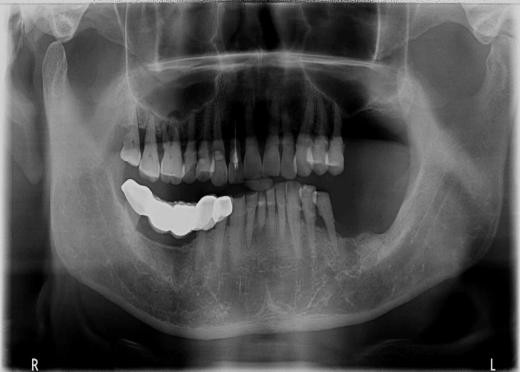

赖仁发教授经典案例:没有条件种,创造条件种

赖仁发教授经典案例:“沙漠”上创造出绿洲

种植体有长,有短,有细,有粗

因为种植牙,生活更美好